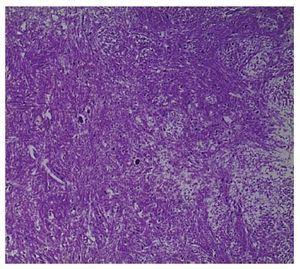

In the outward appearance, jaundice and generalized edema drew attention. The abdomen was distended and, upon opening of cavities, 500 ml of acetic fluid was seen. The liver was slightly retracted, weighed 720 g vs. 760 g and demonstrated congestive splenomegaly (300 g vs. 73 g). The liver showed softening but, on sectioning, large areas of necrosis were observed in 70% of the parenchyma (Fig. 1) that was confirmed microscopically (Fig. 2). The images show the collapse of the parenchyma with the disappearance of hepatocytes in the lobules with only the bile canaliculi and portal spaces visible. Electron microscopy studies were done and determination of copper in the liver tissue, but no evidence of viral inclusions, storage disease or data compatible with Wilson’s disease were found.

Figure 1 Macroscopic aspect of the liver that shows cholestasis and extensive necrotic zones.

Figure 2 A) Panoramic view that shows extensive necrosis of the parenchyma and hemorrhagic zones (HE 10x). B) Approach where extensive necrosis of hepatocytes is observed with collapse of the lobules; only preserved canaliculi and bile ducts are preserved (HE 40x).